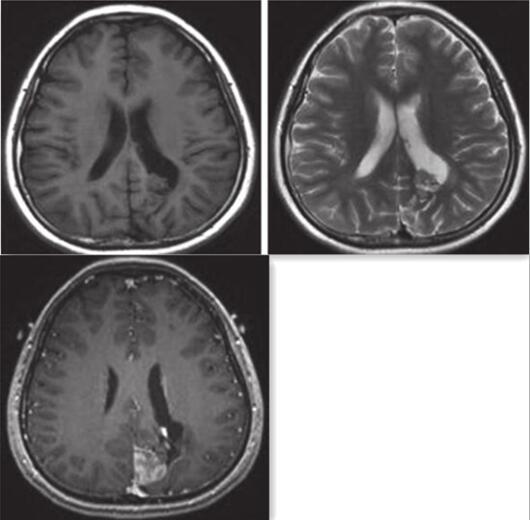

图3 MRI示左顶叶异常信号团块表现同2015-3-18相仿,团块向左前方突入左侧脑室后角

图4 MRV提示上矢状窦近窦汇上方显示不连续,提示受压改变